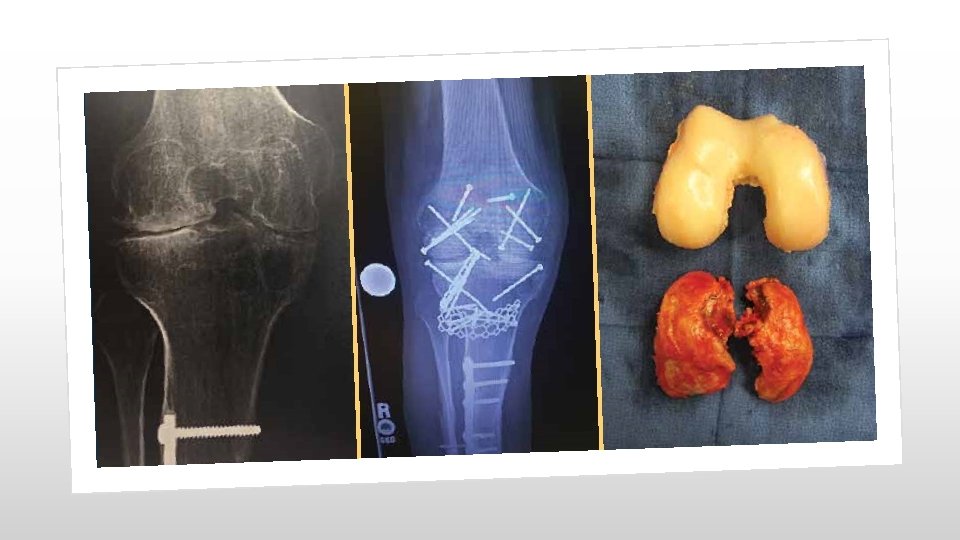

Arthrography When the provider performs a radiographic arthrography, report 73580 (Radiologic examination, knee, arthrography, radiological supervision and interpretation).

Arthrography Change for Common Code Arthrography code 27370 (Injection of contrast for knee arthrography) will be deleted and replaced with 27369 (Injection procedure for contrast knee arthrography or contrast enhanced CT/MRI knee arthrography). If you need help selecting the correct image guidance codes, look no further than the detailed parenthetical guidance. # 27369 $134. 91 $41. 27

Fluoroscopic Needle Guidance When the provider uses fluoroscopic needle guidance (77002) for an enhanced computed tomography arthrography, report 77002 and 73701 (Computed tomography, lower extremity; with contrast material[s]) or 73702 (…; without contrast material, followed by contrast material[s] and further sections). If fluoroscopic needle guidance is used for an enhanced magnetic resonance arthrography use the needle guidance code and 73722 (Magnetic resonance [eg, proton] imaging, any joint of lower extremity; with contrast material[s]) or 73723 (…; without contrast material, followed by contrast material[s] and further sequences).

CPT codes 20932 -20934 were added for allografts. CPT 20932 includes templating, cutting, placement and internal fixation; osteoarticular, whereas CPT 20933 is hemicortical, intercalary, partial and CPT 20934 is hemicortical, complete. Allografts